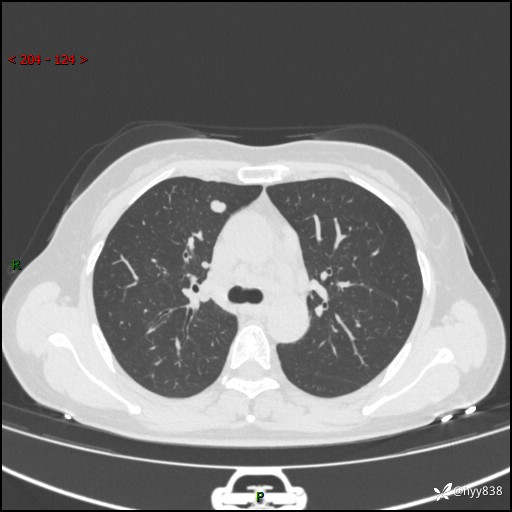

【患者信息】:58岁/女

【主诉】:体检发现肺结节

【检查】:胸部CT平扫+增强

结节病 (44)

小细胞癌 (19)